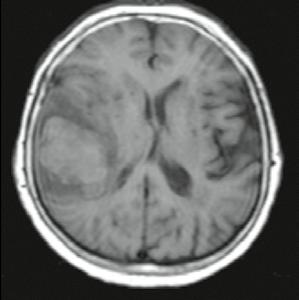

Muž, 61 let. Ischemie ve vertebrobazilárním povodí, dvakrát prodělal infarkt myokardu (IM), v anamnéze kardiomyopatie, hypertenze. Náhlá porucha vizu, nauzea, vomitus, hypakuze, vertigo, nemůže se sám postavit. Objektivní vyšetření: dezorientován, cerebelární syndrom vlevo, centrální vestibulární syndrom, levostranná hemiparéza.

Obr. A1.1–A1.4 Trombóza a. basilaris, akutní ischemické změny vertebrobazilárního povodí (pons, pedunculus cerebri medius dextra, parietookcipitální oblast).

Šipka v obrázku A1.2 – nezobrazilo se vertebrobazilární povodí